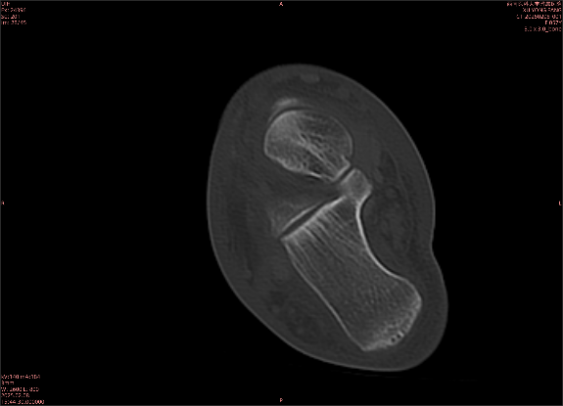

為什么DR和CT基本無法診斷?(專業(yè)科普)

由于無骨皮質(zhì)中斷,尚不足以引起X線衰減系數(shù)的明顯改變,X線平片無異常征象;CT在顯示骨皮質(zhì)及軟組織異常方面明顯優(yōu)于傳統(tǒng)X線,特別是三維重建能夠有效的評(píng)價(jià)復(fù)雜骨折,骨外傷CT檢查應(yīng)用廣泛,但CT對(duì)隱性骨折的顯示亦極為有限。

舉例圖像

圖2

專業(yè)解釋看不懂沒關(guān)系,大家看圖1和圖2就可以了,這是同一個(gè)患者跟骨的磁共振和CT圖像,圖1的紅色箭頭指示的黑線就是磁共振圖像顯示的骨折線,一目了然。而對(duì)比圖2的CT圖像上并未顯示異常。